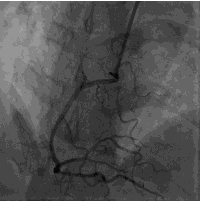

造影结果1:右冠近中段原支架未见明显狭窄。

![]()

造影结果2:左主干正常,左前降支近段100%闭塞,回旋支中远段80%~90%狭窄。

造影结论及应对策略:本病例行冠脉造影发现: 右冠近中段原支架未见明显狭窄,左主干正常,左前降支近段100%闭塞,回旋支中远段80%~90%狭窄。立即行前降支PCI术。